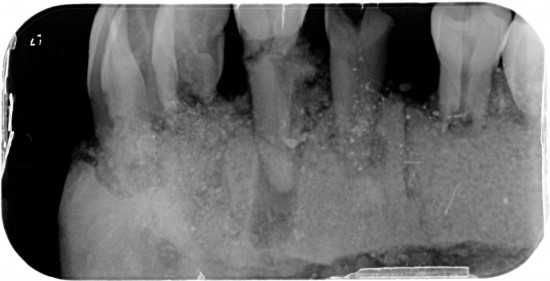

Dit kaakje werd door mijn tandarts grondig bekeken en róntgen foto,s van gemaakt .

Met zijn  langdurige ervaring  uit zijn eigen praktijk. Kunnen namelijk  Molaren verkeerd om zitten. (zie 1ste  molaar linker kaak)

Tevens kunnen er zowel  tanden teveel of te weinig voorkomen .( zie 5 snijtanden ) . De 5de premulaar en hoektand lijken maar een  tand  te zijn , zie rechterkaak. Rontgenfoto wijst echter uit dat het toch 2 aparte tanden zijn .